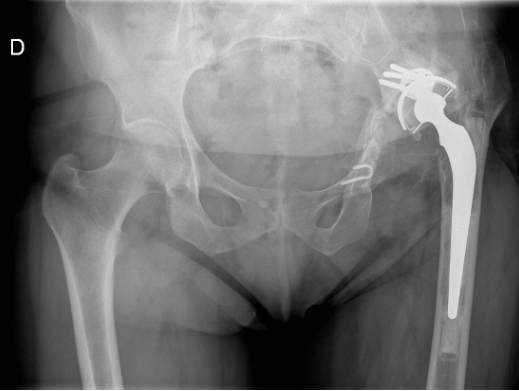

Case report n°6

A 67-year-old female Left THA in 2006, osteonecrosis

- A 2-month history of hip pain

- Report of foot wound 4 months previously complicated by erysipelas treated with oral amoxicillin

- No fever

- WBC 3000, CRP 52

- Bacteraemia MSSA

- Subacute sepsis assumed to be of haematogenous origin

- Course unclear

- Acetabular loosening with implant migration? (Figure 7)

One-stage revision: (Figure 8)

- Acetabular reconstruction with Kerboull cross-plate + bone graft

- Femoral window fixed with cerclage wiring

- Locking long stem and weight-bearing from day 1

- MSSA treated with Oflocet + Rifadin

Recurrence of acute infection after 1 month: (Figure 9)

- Lavage and revision of moving parts

- Negative cultures on ATB

- Treatment with IV Claforan + Daptomycin via PICC line for 3 months

- Follow-up at 18 months OK